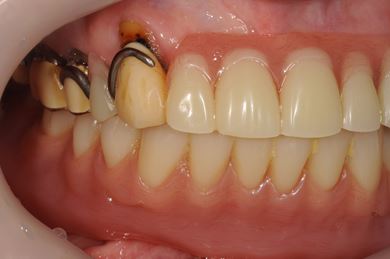

インプラント治療+オーバーデンチャー

| 性別/年齢 | 女性 / 85歳 | ||||||||||||||||||||||||||||||||

| 主訴 | 義歯の調子が悪い。 | ||||||||||||||||||||||||||||||||

| 治療方針 | 下顎に2本インプラントを埋入し、アタッチメントをつけて、オーバーデンチャーを装着し、はずれにくく、安定した義歯を装着する。 | ||||||||||||||||||||||||||||||||

| 治療内容 | インプラント2本(テンポラリーインプラント)、アタッチメント、コバルトクロム床オーバーデンチャー | ||||||||||||||||||||||||||||||||

| 総治療費 | 1,540,350円 | ||||||||||||||||||||||||||||||||

| 治療期間 | 5ヶ月 |